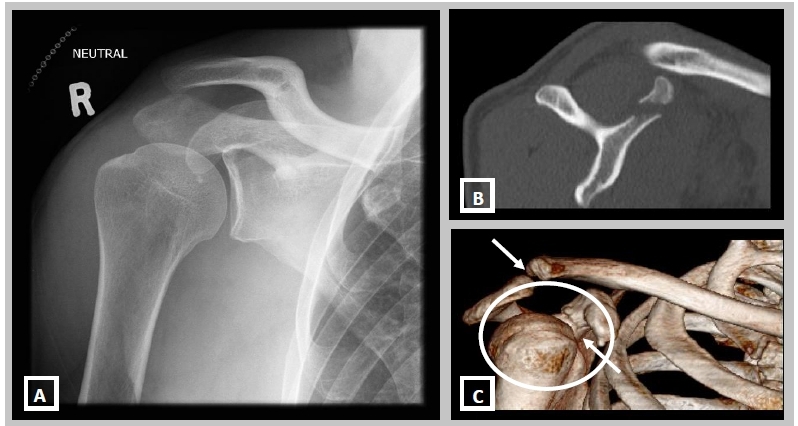

При травмах плеча иногда сложно визуально определить характер повреждений. Для диагностики вывихов, подвывихов, переломов и трещин в костях назначается компьютерная томография.